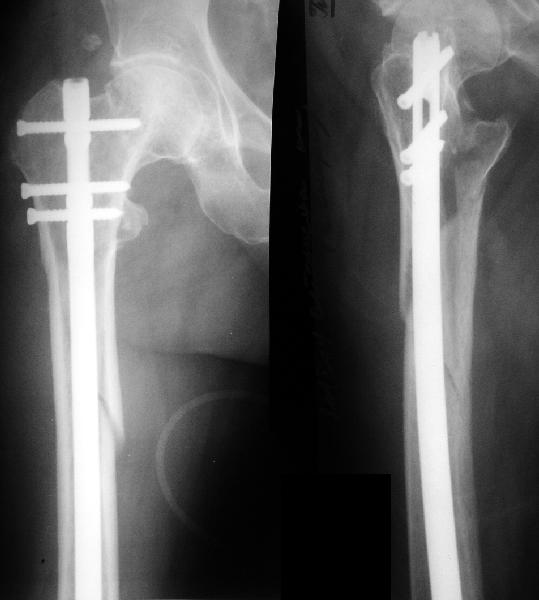

1LateralAnother lateral

Женшина 69 лет оперирована у нас 2 года назад по поводу перелома шейки. Ходила дома без дополнительной опоры, на улице - с тростью.Сегодня утром села мимо табуретки. Поскольку наша бывшая пациентка, сегодня же из области родственники привезли к нам. Картинка в приложении. Какие будут предложения по тактике?

Regarding this specific patient, it is quite difficult for me to discern the exact fracture pattern and therefore treatment suggestions. It appears to be a spiral fracture starting just proximal to the less trochanter and extending distally 6 or more cm into the shaft with medial displacement of the distal fragment. The lesser troch is a seperate fragment. The 2 year old femoral neck fracture appears to have healed in good position I really can't tell where the fracture starts laterally, but presumably it's near the distal most screw.

I can't tell if there is further comminution of the shaft or the greater trochanter. I can barely see the fracture on the lateral radiograph. I'm not sure but I don't see AVN of the femoral head nor OA of the hip. Her overall bone quality appears normal for a 68 year old. I don't see any loosening of the screws but I can't tell for sure.

The fracture extention well into the shaft makes intramedullary fixation somewhat more appealing than plate fixation and contrasts with the case posted by Bill. A reconstruction nail with proximal locking into the femoral head and neck after screw removal and reduction would be reasonable.